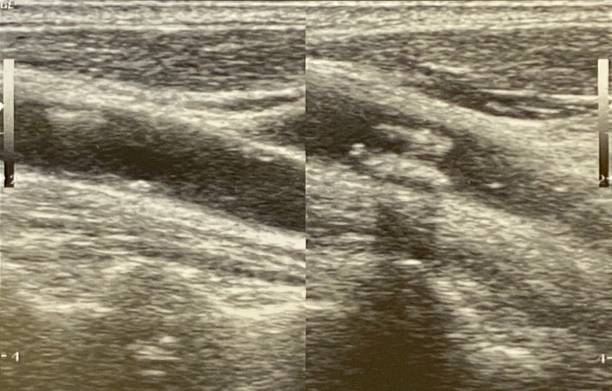

경동맥 초음파 검사는 초음파 기계를 사용하여 경동맥의 상태를 확인하는 검사입니다. 이 검사는 무해하고 비침습적이며, 빠르게 수행할 수 있어 환자에게 불편함을 주지 않습니다. 검사 과정은 다음과 같습니다.

- 환자는 안정된 자세로 앉거나 누워서 검사를 받습니다.

- 의사나 초음파 기술자는 초음파 젤을 사용하여 목 부위에 초음파 프로브를 적용합니다.

- 초음파 프로브는 고주파 소리파장을 방출하여 경동맥의 이미지를 생성합니다.

- 이미지를 컴퓨터 모니터에 표시하여 의사가 경동맥의 상태를 시각적으로 확인할 수 있습니다.